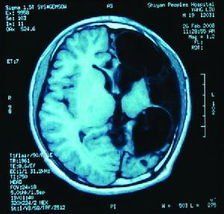

CT可見內囊基底節區、皮質下白質單個或多數圓形、卵圓形或長方形低密度病灶,邊界欠清晰,無占位效應,增強可出現輕度斑片狀強化;CT檢查最好在發病7日內進行,以除外小量出血。MRI可顯示腦幹腔隙病灶,呈T1低信號、T2高信號,MRI腦橫斷面、矢狀位和冠狀位掃描可準確定位病灶。CT和MRI也可能未發現病變,但可排除其他原因導致卒中。因受累動脈很小,腦血管造影正常,因此無須做此項檢查。CSF檢查正常,腦電圖也無陽性發現。